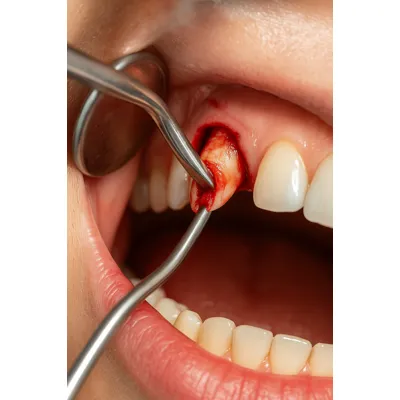

جراحی نوک ریشه دندان با ابزار تخصصی و درمان عفونت لثه

تکنیکهای جراحی:

روش جراحی با فلپ: وقتی ریشه در عمق استخوان گیر کرده باشد، لثه برش داده میشود تا امکان دسترسی فراهم شود.

خارج کردن ریشه با ابزار تخصصی:

دندانپزشک با استفاده از ابزار جراحی مانند الواتور و فورسپس، ریشه را بهآرامی از استخوان خارج میکند تا آسیب به بافت اطراف به حداقل برسد. -